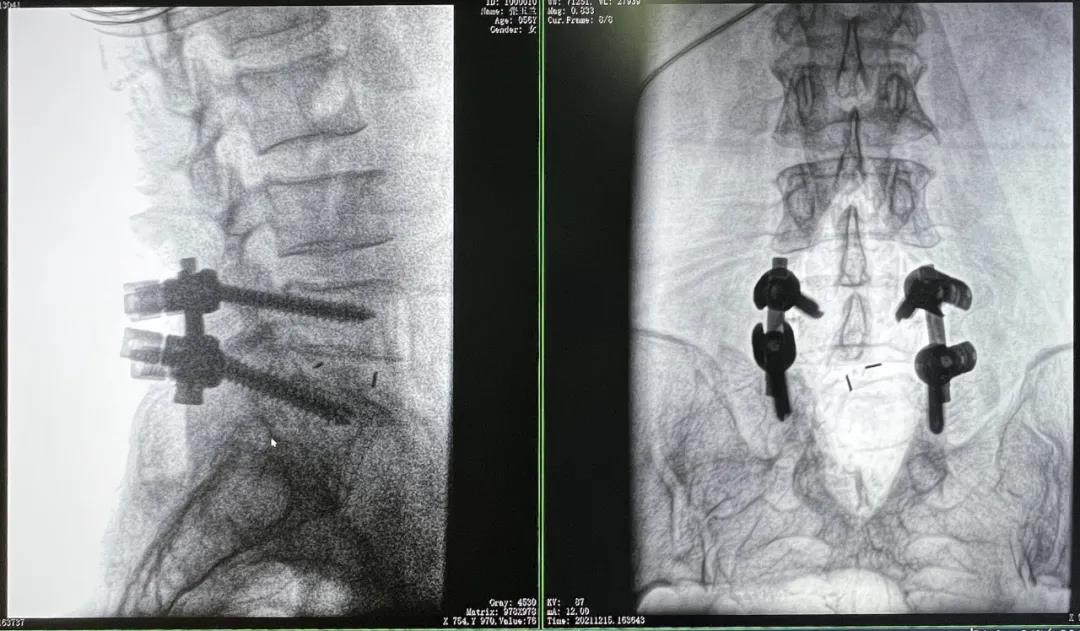

患者1:女性,56歲,L5/S1椎間盤椎板減壓+釘棒固定術

患者下腰部疼痛,活動受限,伴有左下肢疼痛5年,久站或彎腰干活時疼痛加劇,臥床休息后疼痛癥狀緩解,近一個月情況加重,需行椎板減壓+釘棒固定術。

醫生在影像引導下在L5/S1椎弓根處打入醫用螺釘

優質的術中影像輔助螺釘準確植入